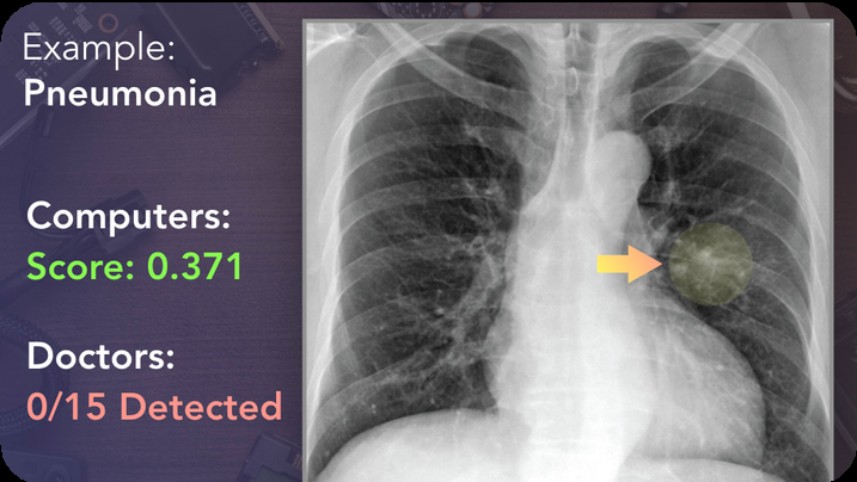

All areas of diagnosis, treatment, and patient care have changed globally, and AI and Doctors need to work together to get best results.

Medical decisions to be taken by doctors with help of AI in current and future and very important for doctors to learn to use and practice getting best patient outcome with AI.

Most infrastructure in hospitals changing to AI enabled and hence requiring doctors to have right skills to be able to provide that outcome for patients.

Doctors use AI tools every day now and patient prefer doctors that know tools to help better treatments.